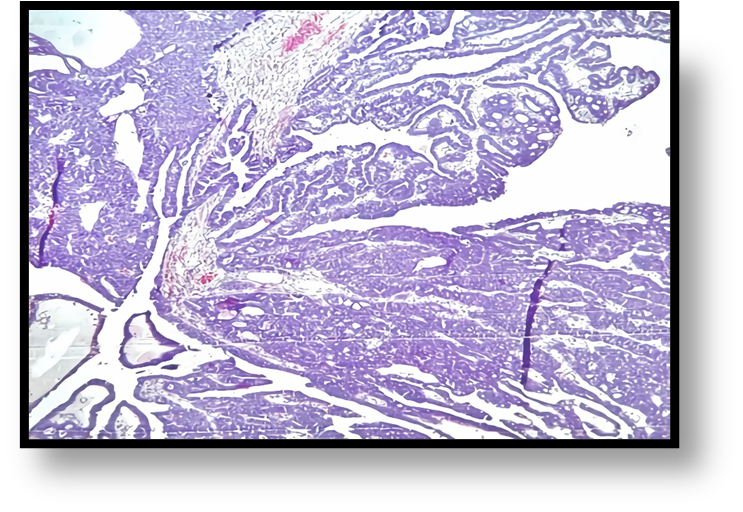

Diagnosed with a benign right adnexal tumor, a laparotomy was performed that revealed a 15x12 cm right ovarian tumor with a cystic component and a 14x5 cm right hydro salpinx with chocolate-like content through its wall (Figure 3). Total hysterectomy plus bilateral salpingo-oophorectomy was performed with a report of ovarian cystadenoma and endometroid adenocarcinoma of the right Fallopian tube. It showed dilation and the section revealed a nodular lesion, in its distal third, with a papillomatous appearance, white-yellowish, of a soft, sessile consistency, with endophytic growth of 2x1.5x.2cm (Figures 4, 5). The microscopic study showed a neoplasm of epithelial origin with a glandular, cribriform, papillary and even solid growth pattern that did not infiltrate the underlying capsule, (Figures 6, 7, 8).

Figure 6: Photomontage microphotographs of nodular lesion corresponding to Endometrioid adenocarcinoma of the uterine tube.

Figure 7: Photomicrograph 5x. Endometrioid adenocarcinoma showing papillary formations with glands and neoplastic cribriform formations.

The microscopic description of this neoplasm is characterized by showing an architecture that varies between glandular, papillary and solid formation with cells showing endometrioid differentiation [7, 10, 13]. In our case, the microscopic study showed a nodular endometrioid carcinoma with papillary formations, a solid, cribriform pattern and with few mitoses, characteristics that correspond to endometrial endometrioid carcinoma [2.8].